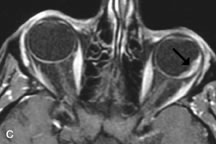

PATIENT PREPARATION Before MRI is performed, patients must be screened and prepared to avoid the potential hazards associated with the strong magnetic field. Patients who have ferrous aneurysm clips or cardiac pacemakers, who depend on life-support equipment, or who retain a possible metallic intraocular foreign body are not candidates for this imaging modality. MRI cannot be performed on obese patients who cannot fit into the bore of the magnet. Patients who are claustrophobic may not tolerate a prolonged period of study within the confines of the magnet, whereas others might do well if given a mild sedative. All worn metallic objects (e.g., necklaces, watches) should be taken off, credit cards set aside, and eye makeup removed before entering the room containing the magnet.5,20,34,35,36 NORMAL ORBITAL ANATOMY T1-weighted images provide the best anatomic details of the orbit because they display superior contrast resolution between normal structures (see Fig. 8). The vitreous has a long T1, resulting in an intermediate signal similar to brain, whereas the crystalline lens and sclera appear dark because of a longer T1 and short T2. The extraocular muscles, like all skeletal muscles, demonstrate a moderately long T1 and short T2 and highly contrast with the intense signal of the surrounding orbital fat (adipose tissue has an extremely short T1). The lacrimal glands appear as mottled areas of reduced intensity of the signal from the orbital fat in the lacrimal fossa. The optic nerves are seen with the same signal intensity as brain white matter and are hypointense relative to the orbital fat because their Tl is longer than the Tl of fat but shorter than the Tl of water. Cortical bone is not well delineated because it contains little free water, yielding minimal signal in MRI, and thus appears dark on all pulse sequences. This feature explains why MR images of the orbital apex and intracanalicular portion of the optic nerves are superior to comparable CT scans. Partial volume averaging of the bones in these regions obscures soft tissue details on CT images, whereas MRI reveals the signals only from the soft tissue structures with no cortical bone input. Bone marrow, on the other hand, is seen as a relatively intense signal because of its high fat content (see Fig. 8).37,38 T2-weighted pulse sequences are not ideal for imaging normal anatomy; however, they are particularly useful in revealing pathologic conditions (see Fig. 9). T2-weighted studies are most easily recognized by a bright vitreous signal. ORBITAL DISEASES Vascular Lesions Cavernous hemangiomas appear as well-circumscribed, smooth, usually intraconal masses that are isointense to muscle on T1-weighted images and hyperintense on T2-weighted images (Fig. 12). Patchy early enhancement is typically followed by diffuse, more homogeneous enhancement.39 The internal architecture of the mass, including septation and internal vasculature, may often be appreciated with high-quality orbital imaging.40 Lymphangiomas consist of ectatic vascular channels within a connective tissue stoma with varying degrees of lymphoid cellularity. On MRI, these tumors are typically poorly circumscribed, multicompartmental, and heterogeneous, often showing cystic dilations with fluid levels (Fig. 13). The signal characteristics within lymphangiomas vary considerably, reflecting cystic and solid components and the varying paramagnetic characteristics of blood at different stages of degradation.40–42 Acute hemorrhage appears hypointense on both T1- and T2-weighted formats. Methemoglobin present in subacute hemorrhage (3 to 14 days) leads to hyperintense signal on both T1- and T2-weighted images.41 A small percentage of lymphangiomas appear radiologically indistinct from orbital cavernous hemangiomas.43 Orbital varices are venous malformations that expand with increased systemic venous pressure, such as with Valsalva maneuvers. Because rapid acquisition of images during a Valsalva maneuver is important in imaging such a lesion, conventional or spiral CT is currently the modality of choice.44 MRI is an excellent modality for demonstrating enlargement of the cavernous sinus and dilation of the superior ophthalmic vein in patients with high-flow carotid-cavernous fistulas (Fig. 14).37MRA may be helpful in the evaluation of the venous outflow pattern. The rapidly flowing blood in these vascular structures carries the excited protons out of the section before they can be imaged, resulting in their dark appearance.5 In low-flow dural arteriovenous malformations, MRA may help define the arterial feeding vessels.45 Neural Lesions MRI is more effective than CT in delineating the intracranial optic nerves, chiasm, and optic tracts and, for this reason, is the preferred imaging modality in the evaluation of optic nerve disorders. The spatial relationships and image contrast of the orbital tissues with intraorbital optic nerve tumors is comparable between the two imaging modalities. The normal nerve is isointense to brain and appears enlarged and kinked owing to infiltration of an optic nerve glioma on T1-weighted images. Gliomas appear hyperintense on T2-weighted images and may be heterogeneous owing to cystic areas within the tumor. Contrast enhancement is variable.46 Intraorbital and intracranial optic nerve sheath meningiomas are usually isointense to cortical gray matter on Tl-weighted images and remain isointense on proton density studies (Fig. 15). Gd-DTPA is useful in delineating the intracranial extension of optic nerve meningiomas.7,47 The hyperostosis of bone and calcification associated with meningiomas are not demonstrated as well on MRI studies as on CT scans.20,37 Gd-DTPA–enhanced MRI also appears promising in the study of the permeability of the blood–brain barrier in selected optic neuropathies.22,48 MRI may reveal an enlarged optic nerve and some degree of contrast enhancement in cases of optic neuritis.49 Muscle Disorders Extraocular muscle enlargement in patients with thyroid-associated orbitopathy is demonstrated equally well with CT and MRI studies. However, the superior tissue contrast on MR images reveals better details of the relationships of the optic nerve to the thickened muscles at the orbital apex (Fig. 16).50 In addition, MRI may be able to differentiate between muscles that are enlarged as a result of edema and active inflammation and those enlarged because of fibrosis by their T2 relaxation times.21 Quantitative MRI was not found to be accurate in predicting the success of low-dose orbital irradiation.51 However, a muscular index relating the diameters of the rectus muscles to the bony orbital dimensions was useful in predicting optic nerve compression.52 MRI is also effective in imaging orbital tumors of mesenchymal origin, such as rhabdomyosarcoma, particularly in the assessment of extension into the anterior and middle cranial fossae (Fig. 17).37 The lack of any pathognomonic radiologic features necessitates rapid orbital biopsy when rhabdomyosarcoma is suspected. Osseous Lesions In general, CT is the imaging modality of choice when details of quantity and quality of bone are needed; however, abnormalities of bones can be detected indirectly by MRI. Cortical bone appears black (signal void) on MR images because of its low proton density and free-water content. The absence or discontinuity of the signal void of the orbital walls may represent bony destruction or fracture. Hyperostosis associated with prostate metastases or meningioma is visualized as areas of black smudging.50,53 Diseases in which the bone is replaced by pathologic tissues with a high free-water content, such as fibrous dysplasia, are well demonstrated on MRI. An intermediate signal intensity on T1-weighted images and hypointense signal on T2-weighted images is representative of fibrous dysplasia. Enhancement on post–Gd-DTPA MR scans is seen and is more evident in areas that are less mineralized.54 Cystic Lesions Dermoid cysts appear as rounded, well-defined lesions typically contiguous with an orbital bony suture. The high-intensity signal on T1-weighted images is attributed to the sebaceous-produced lipid contents (Fig. 18).31,50 Mucoceles may demonstrate a hypointense or hyperintense signal on MR images, depending on the concentration of proteinaceous or inflammatory fluid components. The integrity of the bony walls of the expanded sinus cavities cannot be assessed on MR as well as by CT.37,50,55,56 A high-signal intensity on Tl- and T2-weighted images is characteristic of orbital chronic hematic cysts because of the blood-breakdown products within the cysts.57 Trauma Although soft tissue relationships are usually better demonstrated on MRI, the evaluation of craniofacial bony trauma is preferable with CT. For example, prolapse of orbital fat through a fracture site and hemorrhage of adjacent tissues are demonstrated in an MR image, but the actual fractured bone is not imaged. Three-dimensional MRI of the orbit in subacute trauma has been described,58 although its precise role is not currently established. MRI has been suggested to be superior to CT in detecting intraorbital wooden foreign bodies.59,60 In a series of penetrating orbital injuries with organic foreign bodies, however, MRI was able to identify the foreign body in only four of seven cases.61 With an in vitro model for wood foreign body, McGuckin and colleagues concluded that CT was the imaging modality of choice.62 A careful history and, in selected cases, plain films to rule out a metallic foreign body are crucial before MRI is considered in patients with periocular trauma. MRI is particularly helpful in the detection and characterization of subperiosteal hematomas of the orbit (Fig. 19). They are most commonly seen in the subperiosteal space of the superior orbit as well-defined masses following a traumatic injury. The signal intensity varies depending on the acute, subacute, or chronic nature of the hematoma, based on the stage of blood degradation. Fresh hemorrhages are hypointense on T1-weighted images and hyperintense on T2 images. Hematomas that are 1 to 7 days old are hypointense on both T1- and T2-weighted images. T1-weighted images of hematomas more than a week old are hyperintense due to the oxidation of deoxyhemoglobin to methemoglobin, whereas the T2 images remain hypointense.63 Metastatic Tumors Breast carcinoma metastatic to the orbit has been demonstrated to be hypointense to the surrounding orbital fat on T1-weighted studies and hyperintense on T2-weighted images and has an affinity to the extraocular muscles (Fig. 20).50,64 The MRI characteristics of prostate carcinoma metastatic to the orbit have been described as involving the greater and lesser wing of the sphenoid, orbital roof, and optic canal. Diffuse bone hypertrophy with isointense or slightly hyperintense tissue on T1-weighted images represents the osteoblastic carcinomatous bone infiltration. Contrast enhancement is variable on T1-weighted and fat-suppressed images.65 Most other metastatic tumors also have a lower intensity signal on T1-weighted images and appear to displace or infiltrate normal orbital structures; however, their signal characteristics are variable on T2-weighted MR images.66 Many metastatic tumors demonstrate bright contrast enhancement with Gd-DTPA. Infectious Disorders MRI findings of preseptal and orbital cellulitis typically include increased signal intensities on T2-weighted images of the eyelids and orbital fat, respectively, due to the increased water content of the tissues. Since most cases of bacterial orbital cellulitis are associated with paranasal sinusitis, hyperintense signals of the affected sinuses may also be found on T2-weighted images as well as enhancement of polyps and granulation tissue on postgadolinium T1-weighted MR images. Subperiosteal abscess formation may occur due to contiguous spread of infection from the paranasal sinuses and appear on MRI as an area of intermediate signal on T1-weighted and proton-weighted MR images. The abscess may appear slightly hyperintense compared with muscle on T2-weighted scans with the necrotic contents having the greatest intensity.67 MRI and MRV are more sensitive than CT in revealing cavernous sinus thrombosis. Engorgement of the cavernous sinus, extraocular muscles, and ophthalmic veins is seen with hyperintensity of the thrombosed sinuses evident on all pulse sequences. The enlarged, thrombosed superior ophthalmic vein appears less hypointense than the normal contralateral ophthalmic vein, and hyperintensity within the lumen of the vessel may be seen on T1- and T2-weighted MR images.68 Inflammatory and Lymphoproliferative Lesions Inflammatory conditions of the orbit, both idiopathic (inflammatory pseudotumor) and those of known causes, have been found to be hypointense to fat and isointense to muscle on Tl-weighted studies and isointense or slightly hyperintense to fat on T2-weighted images (Fig. 21).50,64,69 The more fibrous or sclerosing varieties have less signal intensity on T2-weighted images. Marked enhancement is seen in pseudotumor infiltrates after gadolinium administration.70 The same signal characteristics are demonstrated in patients with Tolosa-Hunt syndrome, with mass lesions seen in the cavernous sinuses and orbital apices.71 Lymphomas have MRI characteristics similar to those of inflammatory lesions in that they are hypointense to fat and isointense to muscle on T1-weighted images (Fig. 22). They may appear hyperintense to fat on T2-weighted images, perhaps owing to less fibrosis than that seen in orbital inflammatory pseudotumor, although this is not a consistent finding.31,50,66 Lymphoid tumors typically enhance moderately after contrast injection. Unfortunately, studies have shown that tumor density and homogeneity are similar between inflammatory and malignant orbital infiltrates, and MRI cannot differentiate these lesions.72,73 Lacrimal Gland Tumors Lacrimal gland lesions present special problems in diagnosis and management. Pleomorphic adenoma (benign mixed tumor) should not be biopsied, but rather excised in toto. On the other hand, for lymphoma and inflammatory infiltrates, incisional biopsy is more appropriate than complete excision of the lacrimal gland. Thus, preoperative clinical and radiologic evaluation are especially crucial in planning appropriate surgical management. Pleomorphic adenomas demonstrate long T1 and T2 signal characteristics. They may show heterogeneity on T2-weighted images74 and moderate to marked enhancement with contrast.75 Signal characteristics of adenoid cystic carcinoma include hypointensity to fat on T1-weighted images, hyperintensity to fat with increased T2 weighting, and isointensity to fat on proton density-weighted studies (Fig. 23).31,75 Secondary bony alterations of the lacrimal fossa associated with lacrimal gland tumors, such as remodeling (benign mixed tumor) or destruction (adenoid cystic carcinoma), are seen indirectly on MR images; however, bone windows on CT scans provide better delineation of these changes. In contrast to the round or globular appearance of benign or malignant epithelial tumors of the lacrimal gland, lymphoproliferative tumors usually appear to be molding or draping onto the globe and the surrounding bony orbit. LACRIMAL DRAINAGE SYSTEM DISORDERS MRI with surface coils provides excellent spatial resolution and tissue-specific signal intensities of the lacrimal drainage system. These parameters have been found useful to more accurately demonstrate the extent of lesions in the lacrimal sac and differentiate long-standing mucoceles from solid tumors than CT.76 Physiologic studies in patients with tearing disorders now include MR dacryocystography, in which Gd-DTPA is either placed topically in the conjunctival fornix or injected by cannulation into the lacrimal sac. They provide a detailed morphologic and functional analysis of the lacrimal excretory system; however, they are no more sensitive than digital-subtraction dacryocystography or CT dacryocystography.77–79 INTRAOCULAR TUMORS On MRI, uveal melanomas have a typical appearance that helps to differentiate them from other primary and secondary intraocular tumors as well as choroidal detachments. Pigmented melanomas are hyperintense on Tl-weighted images, hypointense on T2-weighted studies, and hyperintense on proton density–weighted examinations (Fig. 24).30,31,50,80–82 These signal characteristics have been attributed to the paramagnetic properties of melanin because of stable free radicals that shorten the T1 and T2 relaxation times. Moderate enhancement is seen on postgadolinium T2-weighted images. Gadolinium-enhanced T1-weighted images are particularly sensitive in detecting choroidal melanomas.83 MRI may be less sensitive in detecting extrascleral extension of tumor than echography performed by an experienced ultrasonographer.84 Tumors metastatic to the choroid are hyperintense on T1- and T2-weighted images.24 The signal characteristics, however, may be similar to those seen with choroidal melanoma. Choroidal hemangiomas, on the other hand, have an intermediate signal on T1-weighted sequences and become hyperintense on T2-weighted images50 as well as proton density–weighted images.81 Retinoblastomas display moderate signal intensity on T1-weighted studies and a low signal on T2-weighted images.31,80,85 Calcification can be easily detected by CT and ocular ultrasonography but is not imaged by MRI.25,50 The presence of optic nerve involvement is best evaluated by MRI. ACQUIRED ANOPHTHALMIA When an eye is removed owing to tumor or trauma, an implant is typically placed in the intraconal space. MRI may be useful in defining the size, shape, and position of such orbital implants.86 Porous hydroxyapatite or polyethylene implants are preferred by many surgeons performing enucleation or evisceration. A porous implant offers the possibility of supporting a motility coupling peg to increase the movement of the overlying prosthesis. MRI with contrast is used by some surgeons to evaluate the degree of fibrovascular ingrowth in hydroxyapatite87 and porous polyethylene88 implants prior to motility peg placement. |